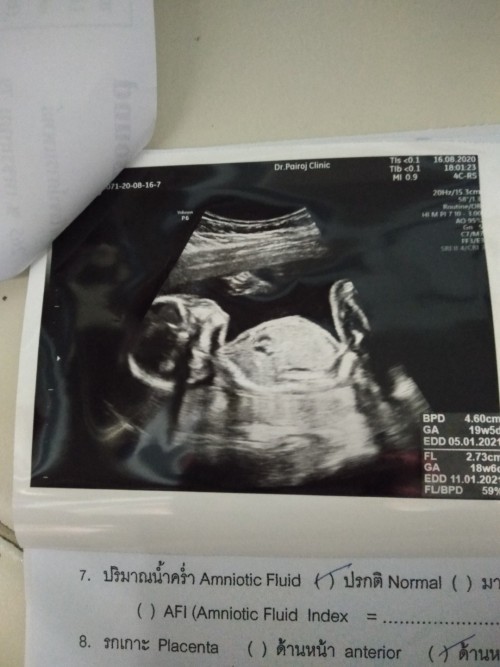

บ้านนี้กำหนด28กุมภา64ค่ะ